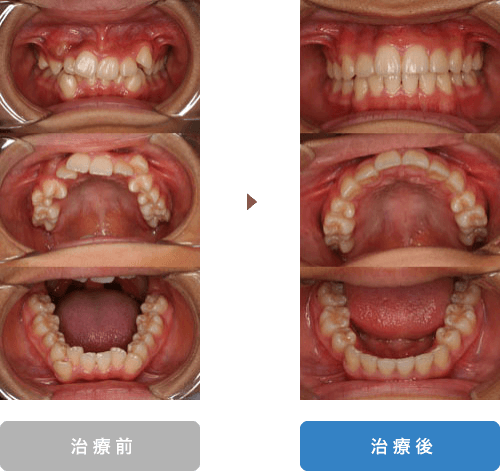

| 主訴 | 歯が重なっている |

|---|---|

| 年齢 | 14歳 |

| 治療期間 | 2年 |

| 通院回数 | 26回 |

| 治療内容 | 顎の大きさに比べて歯が大きく並びきらないので、永久歯がはえてきてから、上下左右一本ずつ抜歯を行いました。その後マルチブラケットシステムにて治療を行いました。見た目だけでなく噛み合わせも良くなり歯ブラシもしやすくなりました。 |

| 抜歯部位 | 上下左右4番抜歯 |

| 治療費 | 約71万円(税込:治療当時税率8%) ※処置料、保定料も含む |

| リスク、副作用 | 骨癒着などにより歯が動かない場合や、 矯正治療によって歯肉退縮する可能性があります。 |

| 担当医 | 長島歯科・矯正歯科 長島雄吾 |